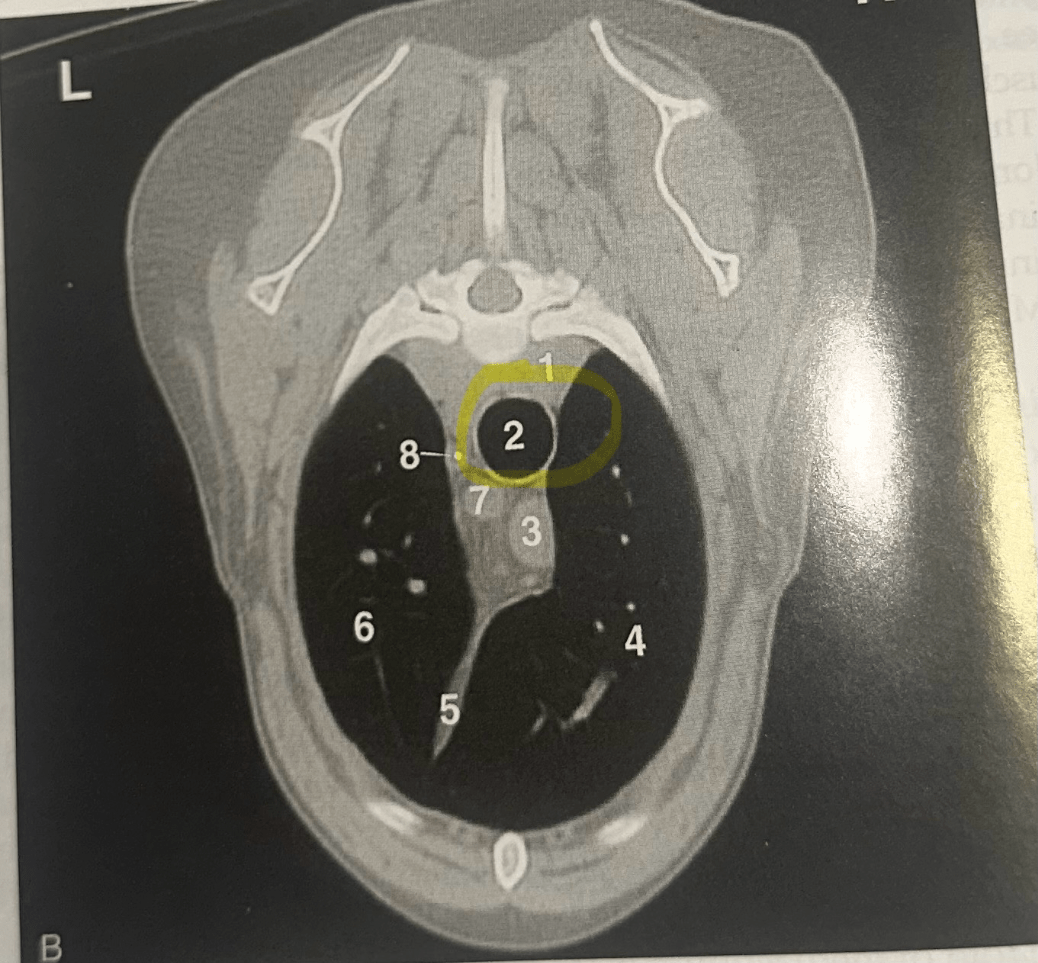

IDENTIFY

Trachea